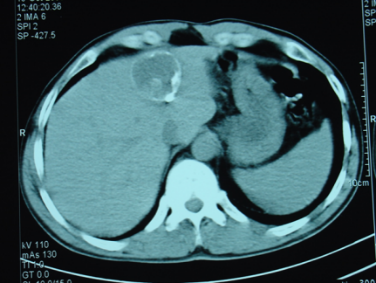

- Diaqnozu dəqiqləşdirmək üçün Qc venaları yoxlanılmalıdır. Bunun üçün dopler USM, KT-angioqrafiya, MRT-angioqrafiyalar və ya kontrastlı venoqrafiya edilir.

- Görüntüləmədə Qc venalarının trombotik tutulması diaqnozu dəqiqləşdirən əlamətdir.

- KT-angioqrafiya;

Qaraciyər venalarının görünməməsi, kontrastlaşmaması və ya trombla tıxanması.

- Görüntüləmədə qaraciyər venalarının tıxanması, I seqment hipertrofiyası ola bilər (xroniki forma);